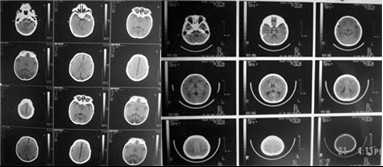

病例图片

![]() |